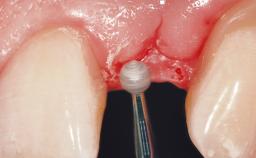

Late Flapless Placement of an Implant in a Maxillary Left Central Incisor Site

A 39-year-old male patient presented with a chief complaint of discomfort and gingival discoloration around his maxillary left central incisor. He was in good general health and was a non-smoker. His past dental history was significant because of the traumatic fracture of tooth 21 in a sporting accident at age 13. Initial dental treatment included endodontic therapy and a full-coverage restoration. The patient became symptomatic 5 years later, when structural failure of the tooth resulted in the dislodgment of the crown. Endodontic retreatment, apical surgery, and post-and-core restoration were performed.

Placement Protocol Early or late implant placement

Bone Volume Deficient horizontally, requiring prior grafting